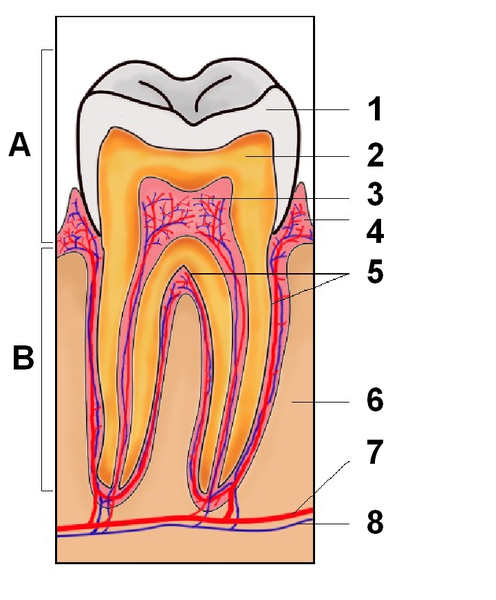

Soubor:Tooth section international.png

Velikost tohoto náhledu je: 496 × 600 pixelů

Obrázek ve vyšším rozlišení (rozměr: 721 × 872 pixelů, velikost souboru: 272 kB, MIME typ: image/png)